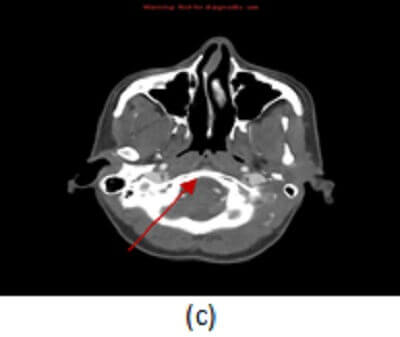

Figure 1: (a)-(c) Sequential axial images from a CT angiogram of the head and neck demonstrate an abrupt caliber change of the distal right V4 segment of the vertebral artery (red arrows) tapering in a “string” sign consistent with the diagnosis of dissection.

MRA and CTA are the most commonly used imaging modalities to evaluate for dissection. Imaging findings common to both modalities include: long segment smooth tapering of the vessel – “string sign”,   vascular occlusion (absence of contrast or signal in the vessel lumen), focal lumen caliber change

and intimal flap with a double lumen for the steno-occlusive form; eccentric dilation of the vessel with luminal contour irregularity for the aneurismal form.